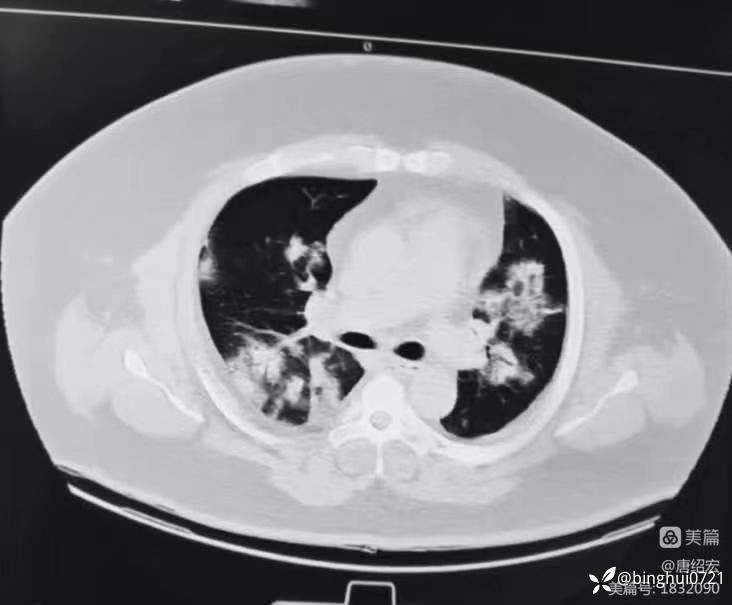

军团菌肺炎的典型CT表现及治疗

男,36 岁,主诉间断发热 1 周,咳嗽伴气短 3 天。入院CT如下:

军团菌肺炎